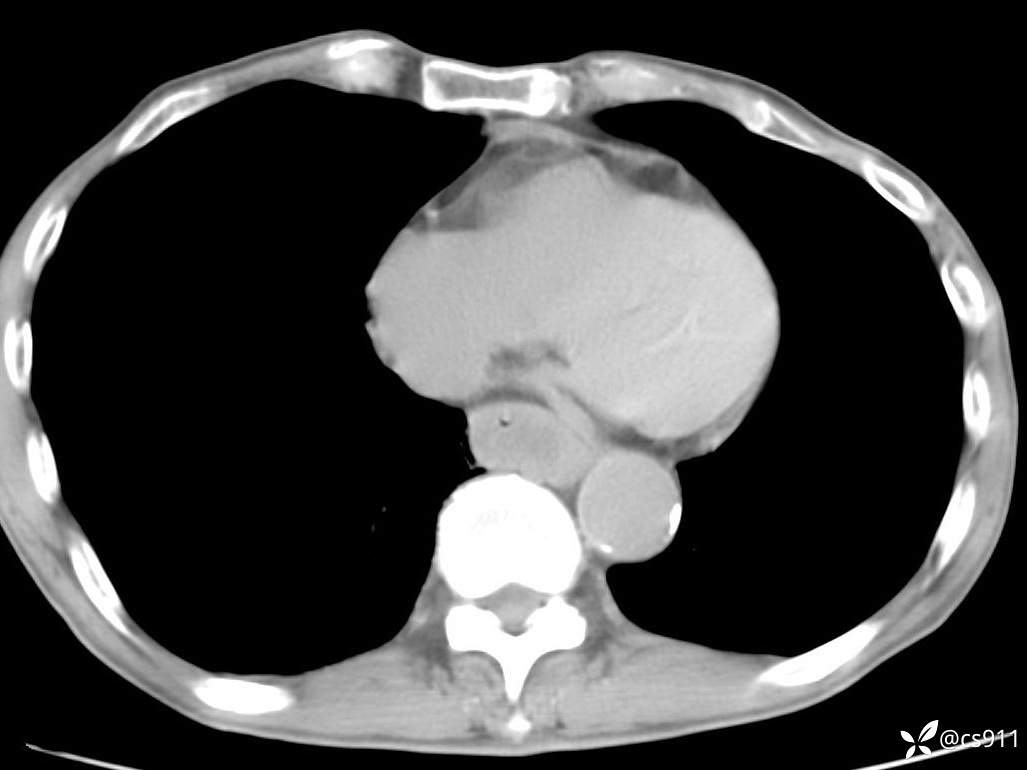

急腹症之急诊CT,原因?答案公布

男,77岁,腹痛、腹胀伴恶心呕吐1天。呕吐胃内容物,非喷射性呕吐,有咖啡色样胃内容物,诉有胃穿孔病史。查体:全腹平,下腹部压痛,全腹无反跳痛,叩诊呈浊音,移动性浊音阴性,肠鸣音减弱,1-2次/分。肛检:直肠未扪及明显肿物,可触及大量粪块。

血淀粉酶(AMY) HH 1859 U/L 35-135